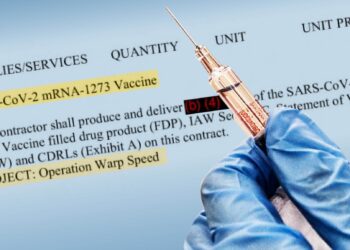

Tampaknya seluruh dunia sudah menjadi gila setelah “varian” Covid19 baru yang disebut Omicron muncul. Propaganda, disinformasi dan ketakutan yang menyebar dari Pemerintah dan Media telah mencapai tingkat absurditas baru. Jadi...